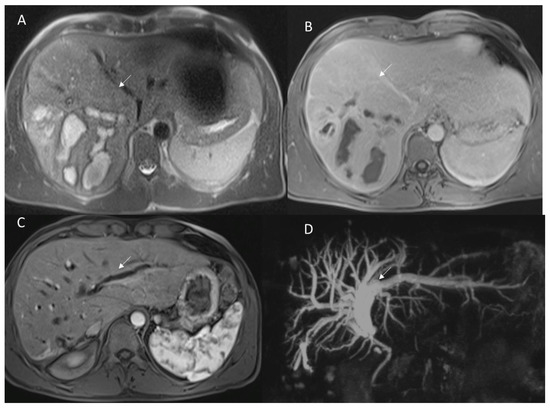

3.1.4. Biliary Injuries

3.2.2. Late Strictures and Ischemic Cholangitis